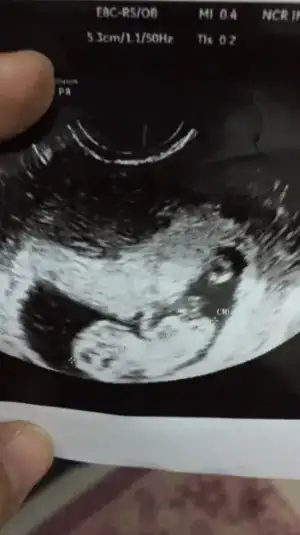

Canım benim usg lerin hiç birinde çıkıntı yok en son yandan usg var ondada hiç bişi yok canım bak ilk foto 10+2 ikinci 12+5

Eklentiler

• 6D4BFC87-77E4-4F1A-931C-F9ECC64D3C0F.webp

6D4BFC87-77E4-4F1A-931C-F9ECC64D3C0F.webp

10,8 KB · Görüntüleme: 48